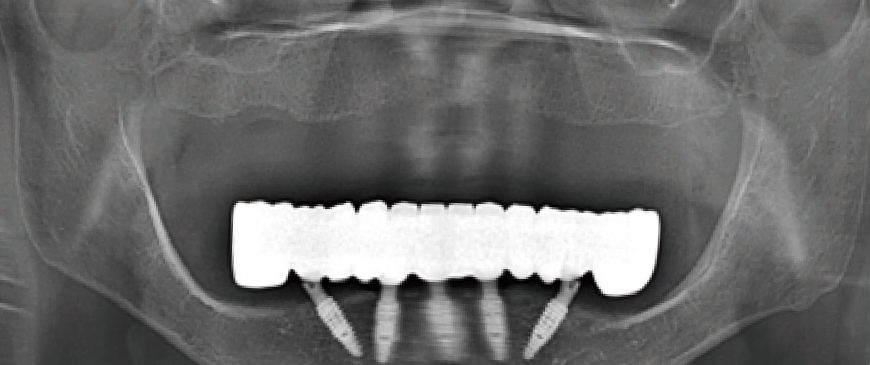

Fig 1

A woman in her late 40s presented with multiple tooth loss and chewing difficulties due to severe periodontal disease. The mandibular anterior region had a thin ridge, but vertical dimension was maintained in both jaws. The upper jaw was to be restored with a partial denture, while the lower jaw was treated with All-on-6 implants to address vertical dimension loss in the left posterior region.

Fig 8

Post-surgery panoramic radiograph. Immediately after the surgery, impressions were taken to prepare provisional prostheses.

Fig 11

Panoramic image when custom abutments and PMMA bridge were placed.